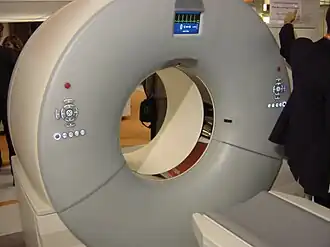

La tomodensitométrie (TDM), dite aussi scanographie, tomographie axiale calculée par ordinateur (TACO), CT-scan (CT : computed tomography), CAT-scan (CAT : computer-assisted tomography), ou simplement scanner ou scanneur pour l'appareil[a], est une technique d'imagerie médicale qui consiste à mesurer l'absorption des rayons X par les tissus puis, par traitement informatique, à numériser et enfin reconstruire des images 2D ou 3D des structures anatomiques. Pour acquérir les données, on emploie la technique d'analyse tomographique ou « par coupes », en soumettant le patient au balayage d'un faisceau de rayons X[1].

Dans les appareils modernes, l'émetteur de rayons X (tube à rayons X) effectue une rotation autour du patient en même temps que les récepteurs situés en face, et qui ont pour fonction de mesurer l'intensité des rayons après qu'ils ont été partiellement absorbés durant leur passage à travers le corps. Les données obtenues sont ensuite traitées par ordinateur, ce qui permet de recomposer des vues en coupes bidimensionnelles puis des vues en trois dimensions des organes. On peut faire ressortir le contraste de certains tissus, en particulier des vaisseaux sanguins, en injectant un produit dit « de contraste » (un complexe de l'iode) qui a la propriété de fortement absorber les rayons X et donc de rendre très visibles les tissus où ce produit est présent (qui apparaissent alors hyperdenses, c'est-à-dire plus « blancs » sur l'image). Grâce aux tomodensitomètres multidétecteurs (ou multi-barrettes) à acquisition spiralée (déplacement lent de la table d'examen durant l'acquisition), on obtient depuis les années 1990 une exploration très précise d'un large volume du corps humain pour un temps d'acquisition de quelques secondes.

Les anciennes générations de scanners à acquisition séquentielle ne permettaient d'acquérir que des coupes successives isolées : la table mobile sur laquelle le patient est étendu était déplacée de quelques millimètres dans la structure circulaire ou anneau puis immobilisée pendant la mesure, et ainsi de suite pour chaque niveau d'acquisition assimilé à une coupe transversale. Les anciennes générations de tubes à rayons X avaient en outre une capacité d'évacuation de la chaleur trop faible pour être compatible avec une cadence d'acquisition élevée.

Dans les scanners spiralés ou hélicoïdaux disponibles depuis les années 1990, l'émission des rayons X est continue durant toute la séquence, la table d'examen progressant à vitesse constante et fixée dans l'anneau. La réalisation de l'examen est beaucoup plus rapide (de quelques centaines de millisecondes à quelques secondes), et plus confortable dans beaucoup de cas (apnée de quelques secondes pour les examens thoraciques, au lieu de plusieurs apnées correspondant à chaque coupe) et fournit une meilleure qualité d'images. La durée de révolution du tube émetteur est passée de 2 secondes à 0,25 seconde sur les appareils de dernière génération. Les acquisitions rapides ont permis le développement de l’angioscanner, technique non invasive d'exploration des vaisseaux sanguins durant le court temps de transit vasculaire du produit de contraste après son injection intraveineuse, supplantant l'angiographie invasive dans maintes indications à visée diagnostique.